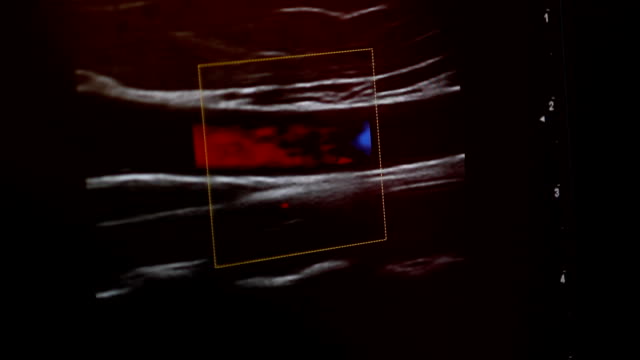

경동맥 초음파 검사는 초음파 기계를 사용하여 경동맥의 상태를 확인하는 검사입니다. 이 검사는 무해하고 비침습적이며, 빠르게 수행할 수 있어 환자에게 불편함을 주지 않습니다. 검사 과정은 다음과 같습니다.

- 초음파 프로브는 고주파 소리파장을 방출하여 경동맥의 이미지를 생성합니다.

- 이미지를 컴퓨터 모니터에 표시하여 의사가 경동맥의 상태를 시각적으로 확인할 수 있습니다.

- 혈류 속도: 혈액이 경동맥을 흐르는 속도를 측정하여 혈액순환에 이상이 없는지 확인합니다.